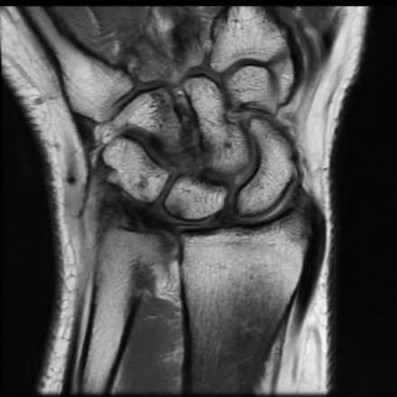

Question 6:

A 22-year-old male falls onto an outstretched hand and sustains a displaced fracture through the proximal pole of the scaphoid. Avascular necrosis of the proximal pole is highly likely due to the disruption of its primary vascular supply. Which vessel provides this critical retrograde perfusion?

Correct Answer: Dorsal carpal branch of the radial artery

Explanation:

The primary blood supply to the scaphoid is from the dorsal carpal branch of the radial artery, which enters the dorsal ridge of the scaphoid at the waist and courses proximally. This retrograde blood flow makes proximal pole fractures highly susceptible to avascular necrosis and nonunion. The superficial palmar branch provides a minor supply (about 20%) to the distal pole.